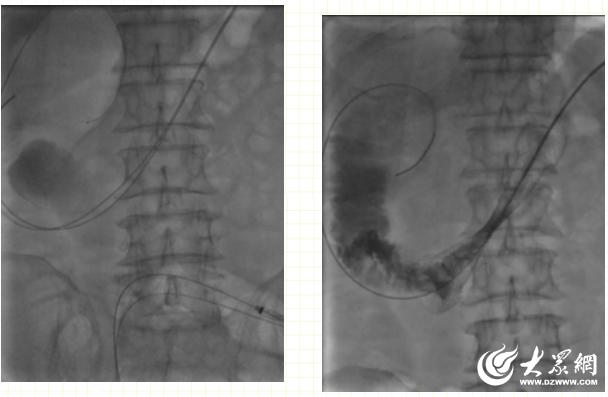

介入医学科主任尹春辉介绍,肠道支架没有什么明显创伤,对于患者来说就像做了一次肠镜检查。医生在DSA(数字减影血管造影机)辅助下,通过一根引导导丝将支架放到梗阻部位,在堵塞的肠腔中撑开一条通道,形成真正意义上的“疏导”。

对于不能进行外科手术及不愿手术治疗的患者,肠道支架也是一种姑息性治疗选择,通过DSA透视下或者内镜下支架治疗肠道恶性狭窄,操作简单、创伤小、并发症少,易被患者接受,可解除梗阻,延长患者生存期,免去患者造瘘后携带“粪袋”的困扰与不便,让患者更舒适地生活。

1.采用DSA透视下微创的方式解除肠道梗阻,患者痛苦小、并发症少。